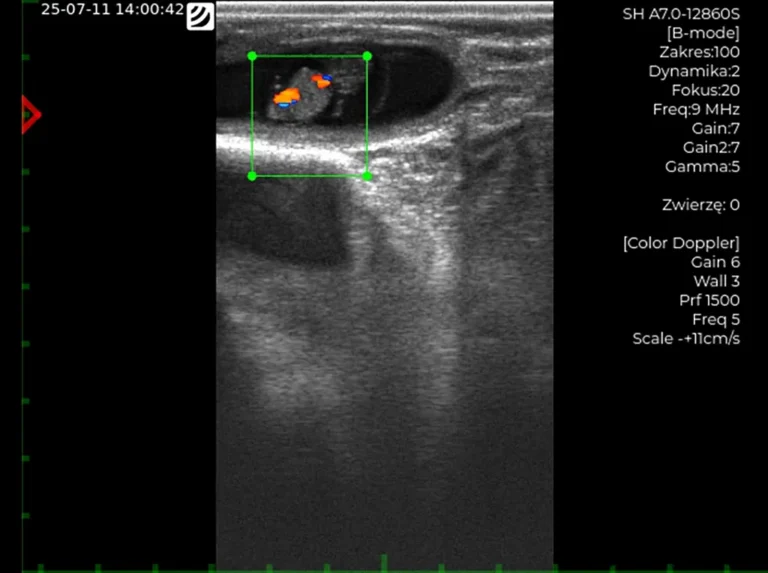

Przenośne ultrasonografy weterynaryjne

do kompleksowej diagnostyki małych

i dużych zwierząt.